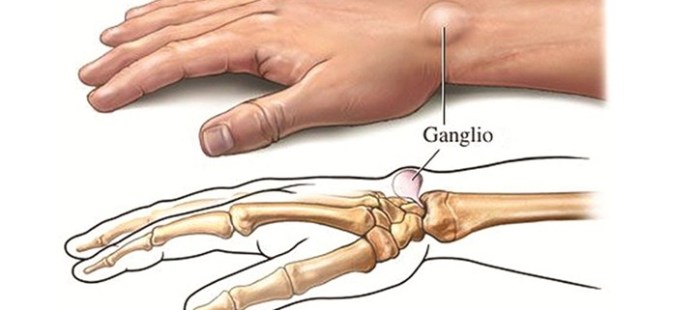

Le cisti, dette anche gangli, sono formazioni rotondeggianti o plurilobulate di consistenza duro-elastica che compaiono spontaneamente al polso e alle dita.

Le cisti, dette anche gangli, sono formazioni rotondeggianti o plurilobulate di consistenza duro-elastica che compaiono spontaneamente al polso e alle dita.